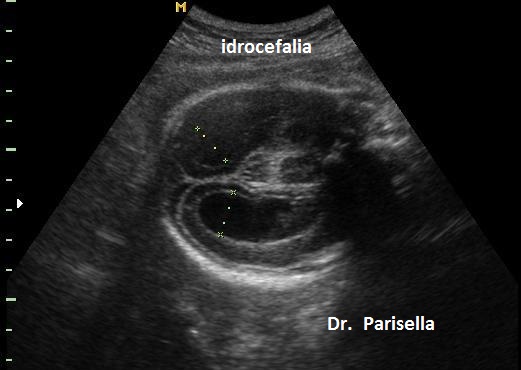

Le lesioni caratteristiche a carico del SNC sono rappresentate  da idrocefalo grave, con ventricoli aperti nello spazio subaracnoideo, ipoplasia cerebrale, anomalie della linea mediana e del setto pellucido (agenesia del corpo calloso); possono essere presenti encefalocele occipitale, una caratteristica conformazione del forame magno “key-hole shaped”, mandibola piccola e naso malformato, labio-palatoschisi. Caratteristica è la polidattilia postassiale alle mani e preassiale ai piedi (l'alluce duplice è altamente caratteristico, quasi esclusivo, di questa condizione morbosa). Segnalati anche piede torto e difetti cardiovascolari (difetti del setto atriale; atrio unico). Come ha segnalato lo studio di Salonen e coll. (1981) condotto su 28 neonati di 18 famiglie, l'esito abituale della gravidanza è la nascita di feto morto o morte in epoca neonatale.

La Diagnosi Prenatale si basa su: 1) assenza di movimenti attivi fetali; 2) polidattilia postassiale alle mani; 3) polidattilia preassiale ai piedi;  4) idrocefalia; 5) polidramnios.